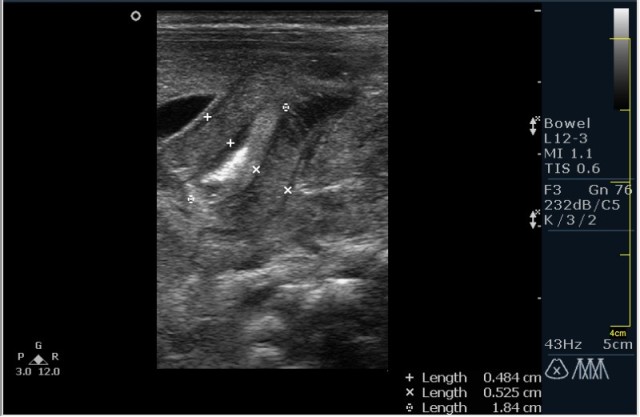

Ребёнок 1 месяц 10 дней от родy, с отсуствием прибавки в весе.

Hypertrophic pyloric stenosis.

Criteria:

1.Pyloric channel > 12 mm in length

2.Muscular layer thickness > 3-4 mm

3.Donuts sign at transverse scanning